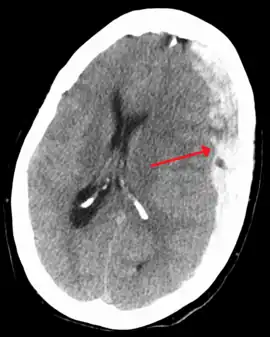

A subdural hematoma demonstrated by CT

It is important that a person receive medical assessment, including a complete neurological examination, after any head trauma. A CT scan or MRI scan will usually detect significant subdural hematomas.

On a CT scan, subdural hematomas are classically crescent-shaped, with a concave surface away from the skull. However, they can have a convex appearance, especially in the early stages of bleeding. This may cause difficulty in distinguishing between subdural and epidural hemorrhages. A more reliable indicator of subdural hemorrhage is its involvement of a larger portion of the cerebral hemisphere. Subdural blood can also be seen as a layering density along the tentorium cerebelli. This can be a chronic, stable process, since the feeding system is low-pressure. In such cases, subtle signs of bleeding—such as effacement of sulci or medial displacement of the junction between gray matter and white matter—may be apparent.

Fresh subdural bleeding is hyperdense, but becomes more hypodense over time due to dissolution of cellular elements. After 3–14 days, the bleeding becomes isodense with brain tissue and may therefore be missed.[20] Subsequently, it will become more hypodense than brain tissue.[21]